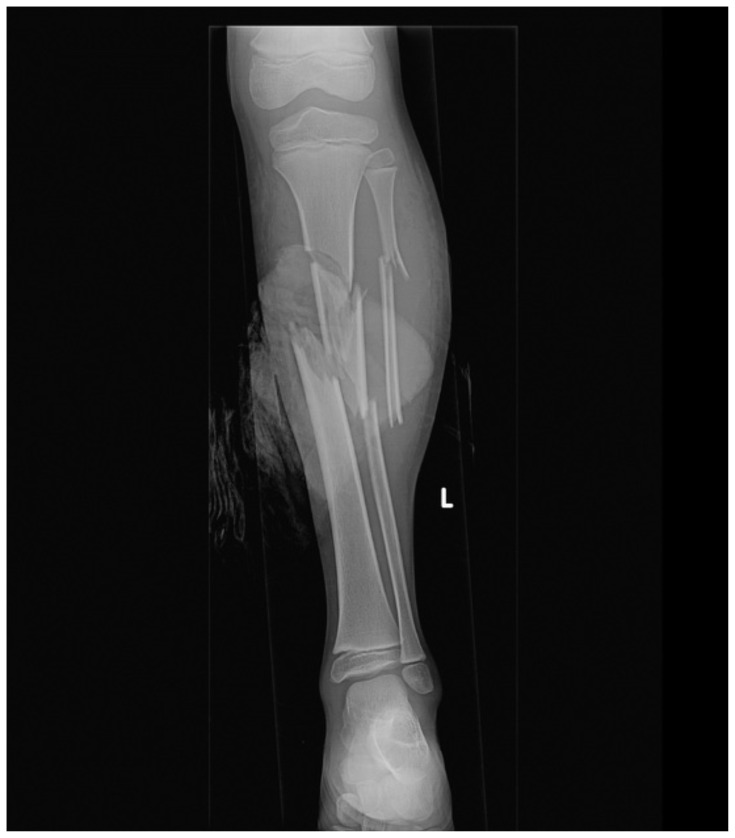

Introduction: Emergency and trauma surgery practitioners routinely perform primary and secondary surveys as a systematic approach to trauma care. While this approach has broad applications, clinicians must also be versed in the nuances of caring for special populations in trauma. One such example is the obstetric patient. The incidence of trauma in pregnancy is increasing and is now the leading cause of non-obstetrical maternal death in the United States.1 Optimal maternal resuscitation depends on an understanding of the significant anatomic and physiologic changes of pregnancy and their influence on airway, breathing, and circulation.2,3,4This case presents a blunt polytrauma with unstable pelvic and lower extremity fractures precipitating hemorrhagic shock and the need for blood product transfusion. Learners must quickly adapt their clinical acumen and consider the influence of an obviously gravid patient on their resuscitation. Implementing and practicing the required skills allows for delivery of high-quality care. This session ensures that learners have a well-rounded understanding of scenarios that could occur in the resuscitation of a pregnant trauma patient.

Educational objectives: At the completion of this simulation participants will be able to 1) perform primary and secondary trauma surveys, 2) assess the neurovascular status of a tibia/fibula fracture, 3) appreciate anatomic and physiologic differences in pregnancy, 4) appropriately order analgesia and imaging, 5) recognize and treat hemorrhagic shock, 6) perform an extended focused assessment with sonography in trauma exam (eFAST) in undifferentiated hemorrhage, 7) identify a displaced pelvic fracture and properly apply a pelvic binder, and 8) obtain and interpret fetal heart rate using ultrasound.